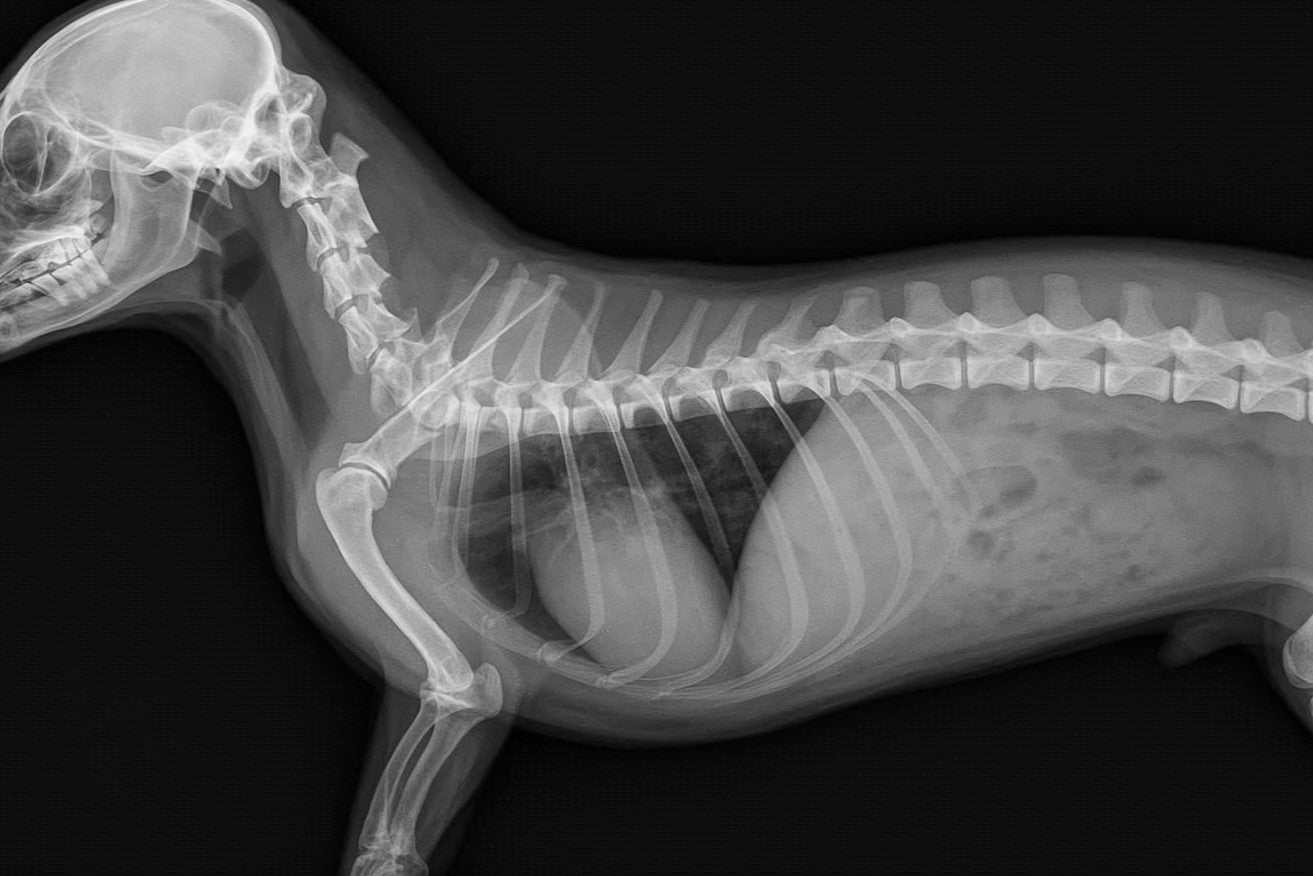

Like many dachshund owners, we faced the daily challenges of caring for a breed whose anatomy is both endearing and complex. From the elongated spine to the short limbs and unique gait, every aspect of a dachshund’s body tells a story of resilience, but also of vulnerability.

As Lulo grew, we began to notice subtle signs: hesitations when climbing, shifts in posture, moments of discomfort that were often dismissed as “normal for the breed.” But what we learned, through veterinary consultations, biomechanical studies, and countless hours of observation, is that these small details are early warnings.

They are the first signs of how a dachshund’s lifestyle, environment, and daily habits can directly affect spinal health and long-term mobility.

This realization became our turning point. We discovered that most pet products in the market were designed with a “one-size-fits-all” mindset, built for generic proportions, not for dogs with elongated vertebral columns and a predisposition to spinal disorders such as Intervertebral Disc Disease (IVDD).